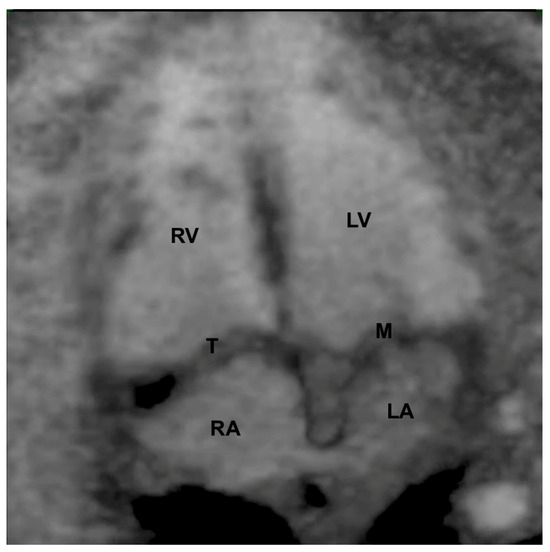

Inversion mode postprocessing in the Spatiotemporal Image Correlation method in a 4-chamber view of a normal heart. LV: left ventricle; LA: left atrium; RA: right atrium; RV: right ventricle; T: tricuspid valve; M: mitral valve.

Grayscale STIC allows the assessment of the ventricular outflow tracts as well as the aortic and ductal arches. In this scenario, the B-flow imaging technique in STIC enhances the weak signals from blood and eliminates strong signals from nearby structures and is potentially superior to color Doppler in the assessment of large vessels and venous connections. B-flow imaging produces images similar to angiographic images (Figure 5 and Video S1). The post-processing inversion mode (inverted flow) is another technique that analyzes fluid structures and inverts the grayscale voxels. The inversion mode allows the reconstruction of ventricles, aortic, and ductal arches, as well as abnormal venous connections and septal defects (Figure 6 and Video S2).